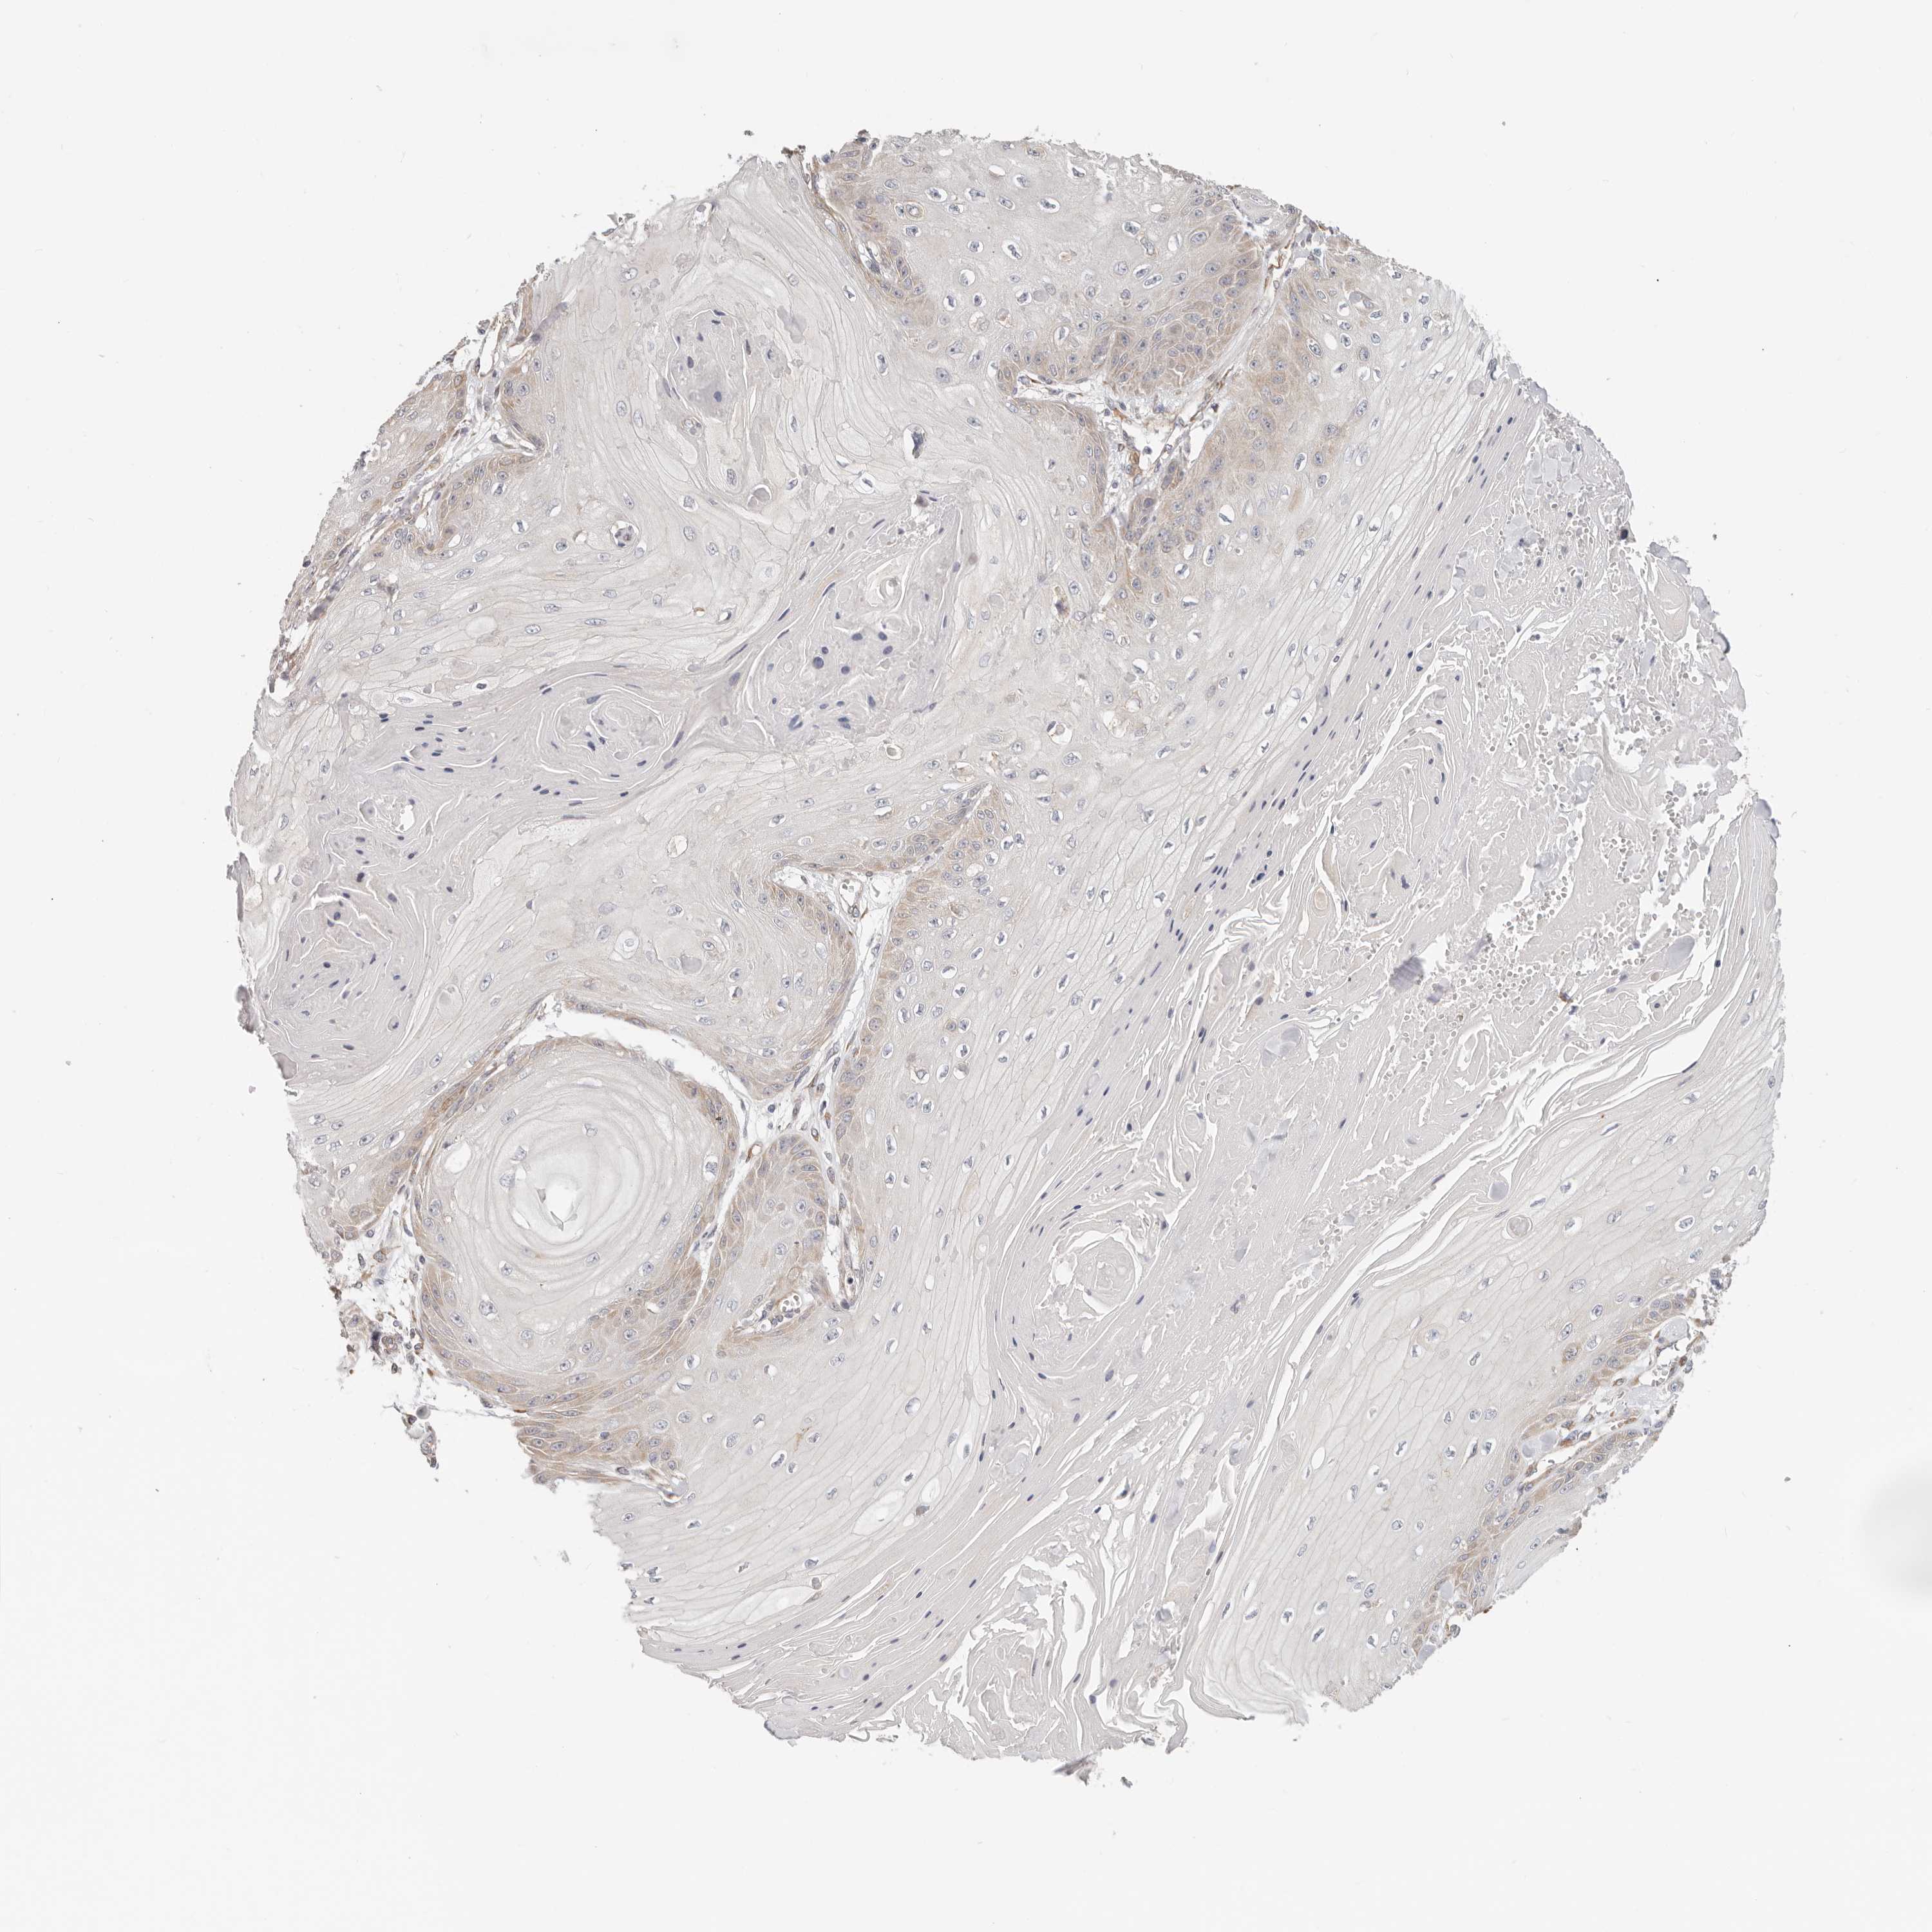

SKIN CANCER - Protein expressioni

A mouse-over function shows sample information and annotation data. Click on an image to view it in a full screen mode. Samples can be filtered based on level of antibody staining by selecting one or several of the following categories: high, medium, low and not detected. The assay and annotation is described here.

Antibody staining in the annotated cell types in the current human tissue is reported as not detected, low, medium, or high, based on conventional immunohistochemistry profiling in selected tissues. This score is based on the combination of the staining intensity and fraction of stained cells.

Each image is clickable and will lead to virtual microscopy that enables deeper exploration of all samples and also displays staining intensity scores, fraction scores and subcellular localization as well as patient and tissue information for each sample.

Basal cell carcinoma

Squamous cell carcinoma, NOS

Squamous cell carcinoma, metastatic, NOS

Adnexal tumor, benign